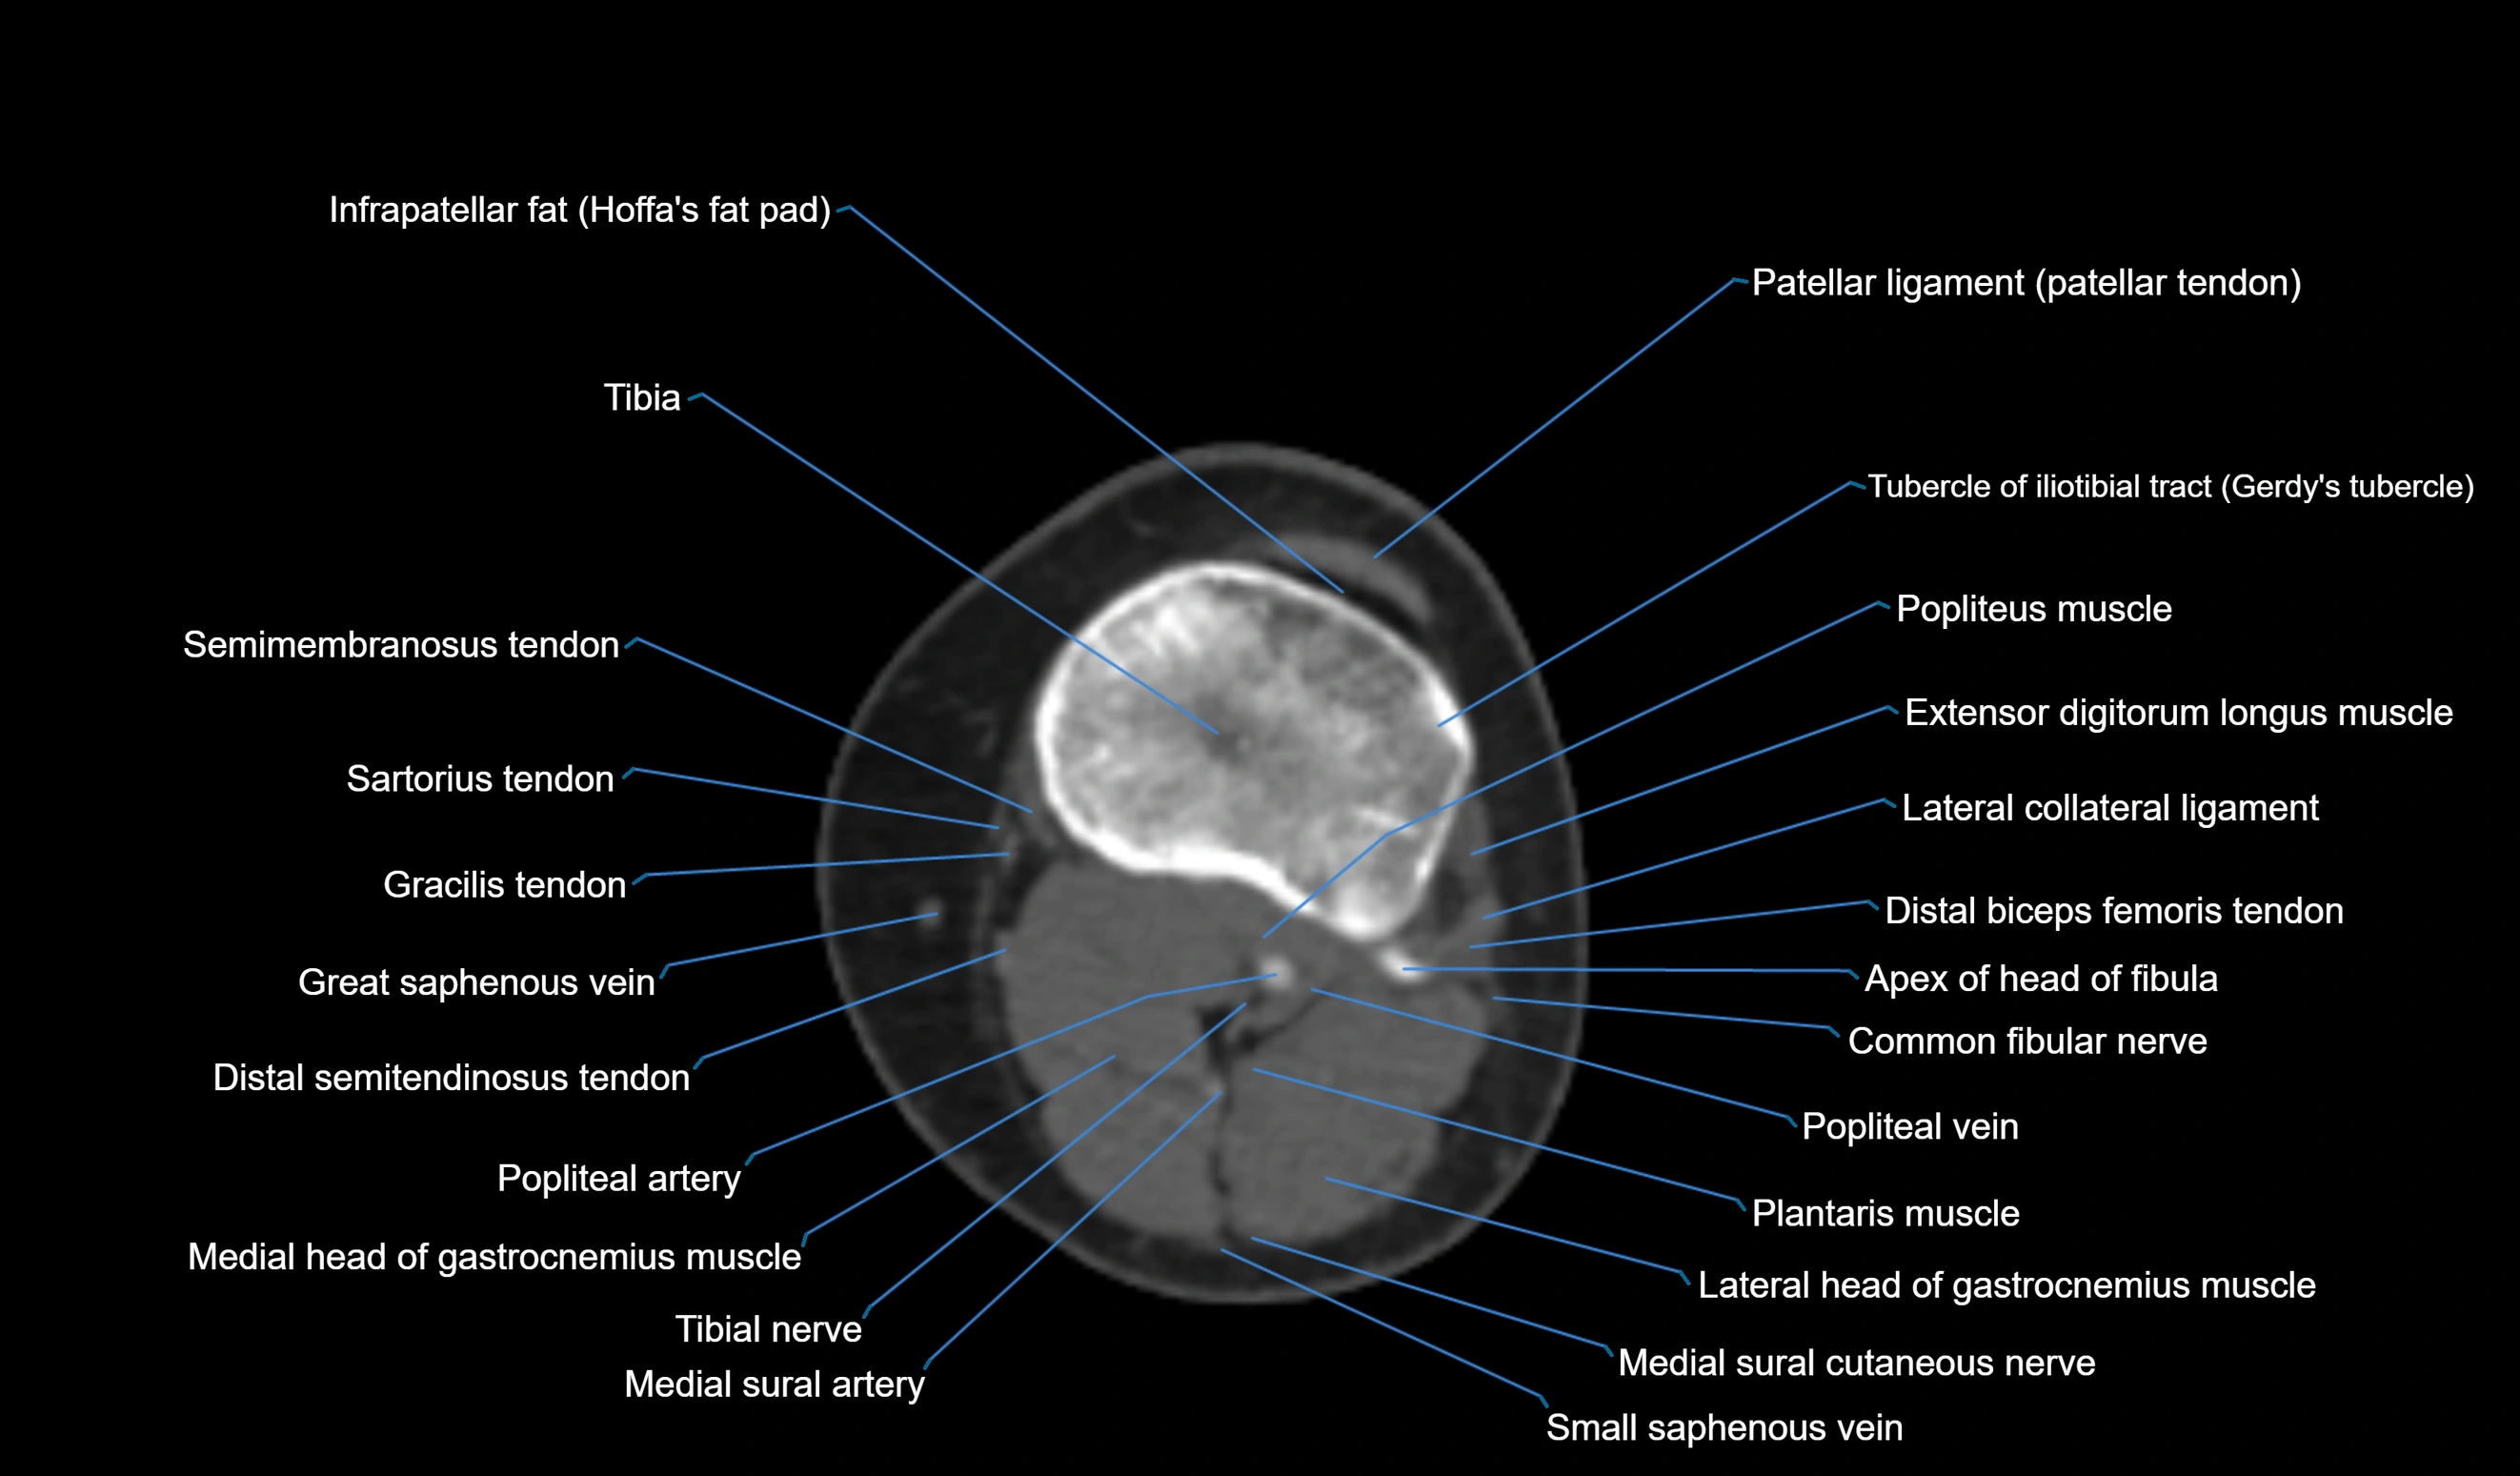

- Apex of head of fibula

- Common fibular nerve

- Distal biceps femoris tendon

- Distal semitendinosus tendon

- Extensor digitorum longus muscle

- Gracilis tendon (Distal)

- Infrapatellar fat pad

- Lateral collateral ligament

- Lateral head of gastrocnemius muscle

- Medial head of gastrocnemius muscle

- Patellar tendon (patellar ligament)

- Plantaris muscle

- Popliteal artery

- Popliteal vein

- Popliteus muscle

- Sartorius tendon (Distal)

- Tibia

- Tibial nerve

- Tubercle of iliotibial tract